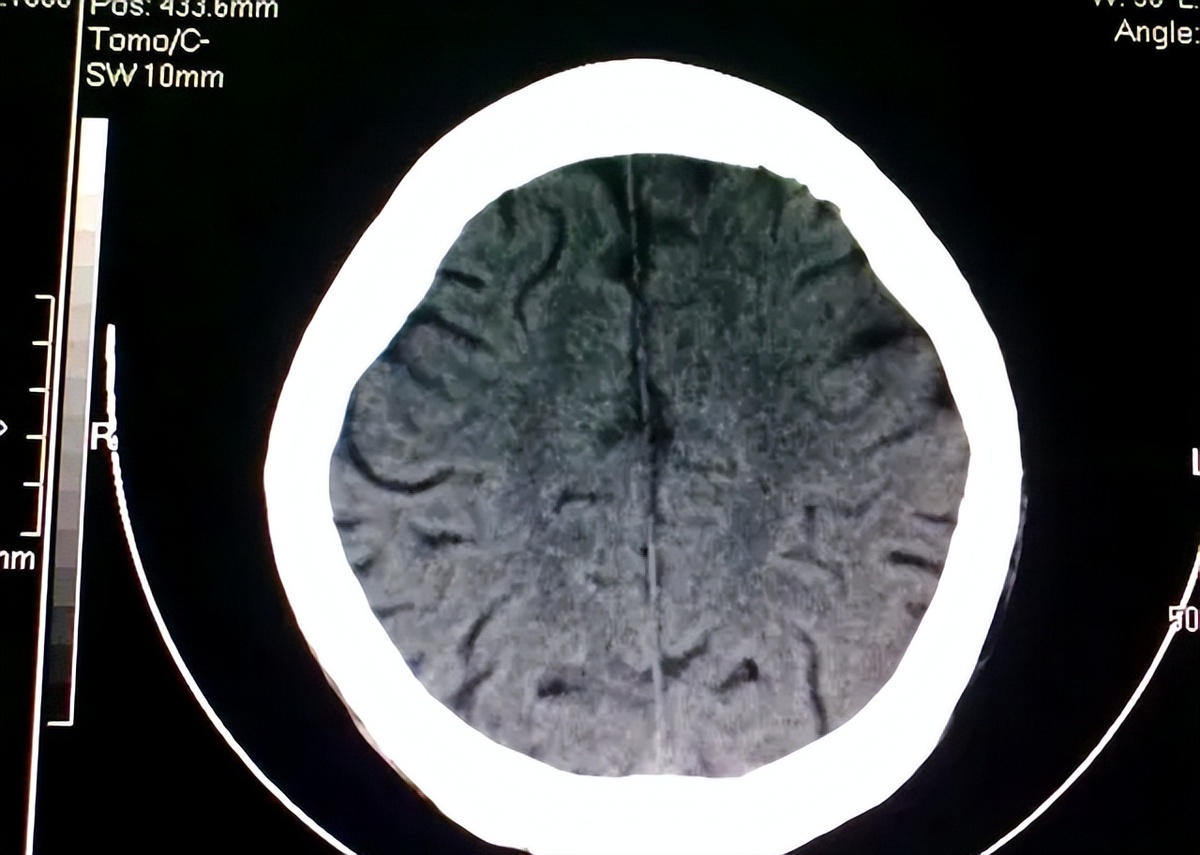

33 года назад людям стало известно об открытии огромной важности. Пациент, страдавший головными болями и эпилептическими припадками, привлек широкое внимание медицинского сообщества. После планового обследования его мозга врачи с удивлением обнаружили, что его мозг был практически замещён жидкой тканью, что свидетельствует о тяжёлом отёке мозга и крайне серьёзном повреждении коры головного мозга. Результаты КТ оказались ещё более невероятными. Внутри его головы не было практически никаких неповреждённых мозговых тканей. Эта ситуация повергла врачей в глубокое замешательство. Как вообще может человек с практически отсутствующим мозгом жить как нормальный человек?

Данный пациент не только женился и завёл детей, но и сдал экзамен на государственную службу. Пока он не приехал лечиться от болезни, будучи взрослым, его повседневная жизнь, казалось, не сильно страдала.